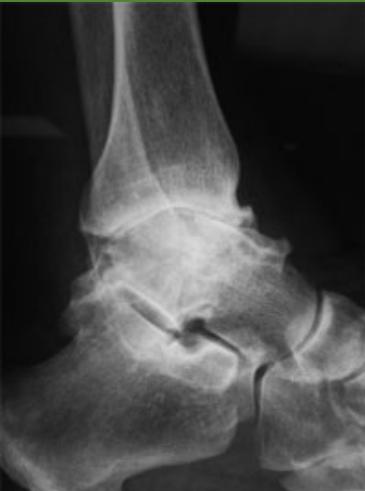

Diagnostic Imaging

Hip osteoarthritis comparison images: * Hip without Osteoarthritis (for comparison)